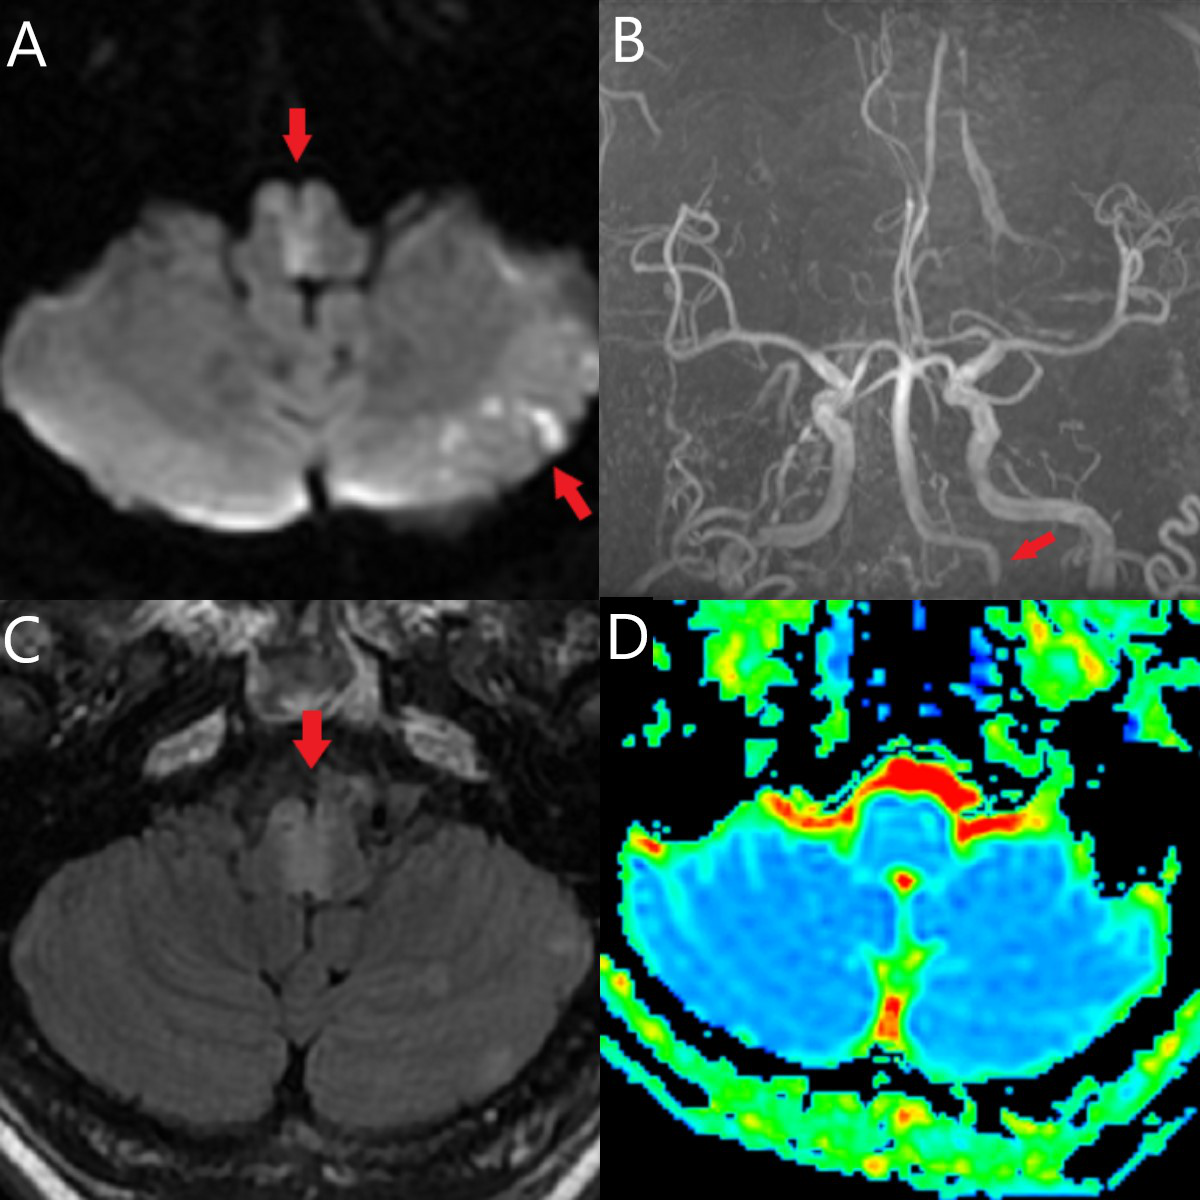

患者术后第1天桥接双抗治疗。查体:双侧肌力4级+,轻度构音障碍,共济失调阴性,面瘫消失。NIHSS评分1分。术后3天复查DWI(图4),可见延髓“心形”梗死(↑所指),左侧小脑散在梗死灶。MRA可见左侧椎动脉血流通畅(↑所指)。术后8天查MRP,未见明显灌注减低。术后9天出院。出院时,患者四肢肌力恢复至5级,吞咽及言语功能明显好转。术后90天电话随访MRS评分0分。

图4. A:术后3天DWI,可见延髓“心形”梗死(↑所指),左侧小脑散在梗死灶;B:MRA提示可见左侧椎动脉血流通畅(↑所指);C/D:术后8天MRP,未见明显的灌注减低。